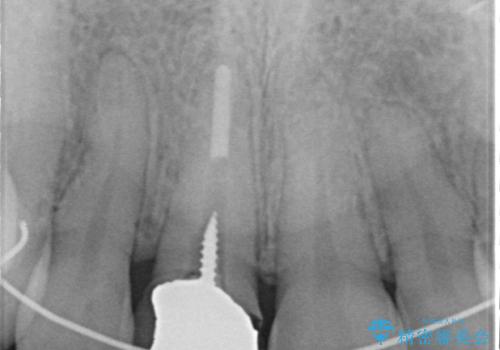

- 以前他院にて保険診療で治療した前歯のやり替え希望の患者様です。

被せものと土台の境目が段差になっています。

ファイバーコアにやり替えて、形を整え直して、

精度の高いシリコーンで型どりしました。

被せものと土台の歯との境目が、歯茎の下に隠れるように調整し、段差もないため、審美性・清掃性のどちらの観点からも理想的な被せものになり、患者様は満足されました。